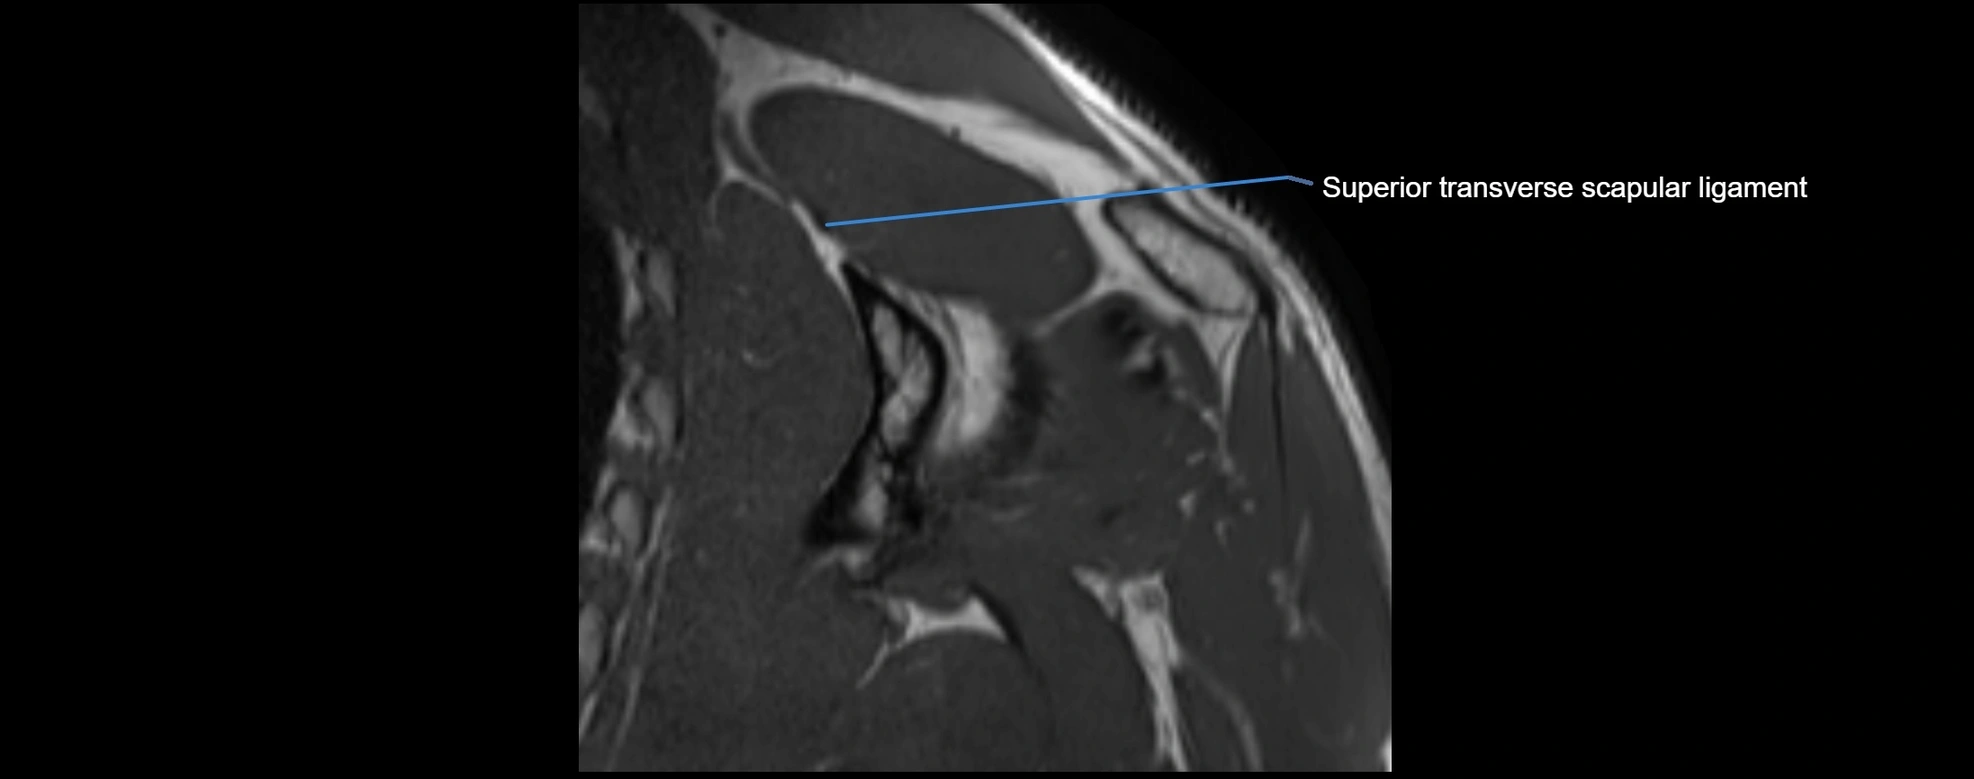

MRI Appearance

• STIR:

• Normal ligament: Dark linear band.

• Injury or inflammation: Bright hyperintense signal in and around ligament fibers.

• Highlights periligamentous soft-tissue edema, especially in acute trauma.

• Proton Density Fat-Saturated (PD FS):

• Normal ligament: Low signal, uniform thickness.

• Partial tear or sprain: Bright signal or contour irregularity.

• Complete tear: Clear discontinuity with bright signal gap and joint effusion.

• Excellent for assessing joint capsule, coracoclavicular ligaments, and periarticular edema.

MRI images

image